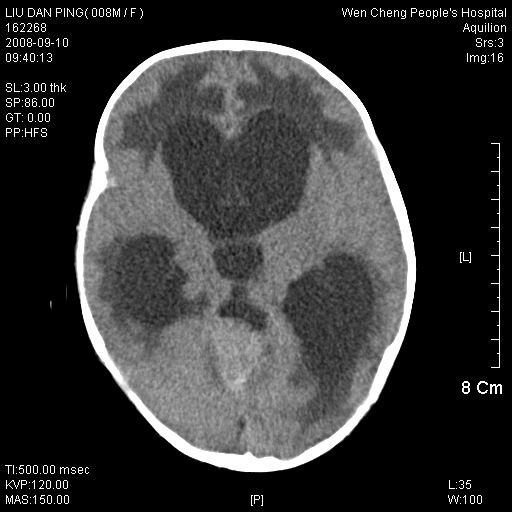

以下是引用卜一在2008-9-10 16:21:00的发言:[br]髓母细胞瘤伴梗阻性脑积水!支持![br]髓母细胞瘤特点:—般直径大于3.5cm,位于后颅凹中线之小脑蚓部。累及上蚓部的肿瘤延伸到小脑幕切迹之上,ct平扫肿瘤多呈均匀一致的高或等密度病灶,增强检查呈均匀一致的强化。病灶中有小坏死时,平扫亦可呈不均匀之混杂密度,注药后有增强。[br]

以下是引用zjzjr在2008-9-10 15:09:00的发言:[br]髓母细胞瘤伴梗阻性脑积水.